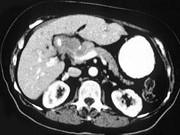

问题 女,40岁,右上腹痛,进行性黄疸,腹部未触及包块,AFP阴性,影像检查如图,最可能的诊断是()

选项 A.肝细胞肝癌 B.胆总管癌 C.胰头癌 D.胰岛细胞瘤 E.慢性胰腺炎

答案 B